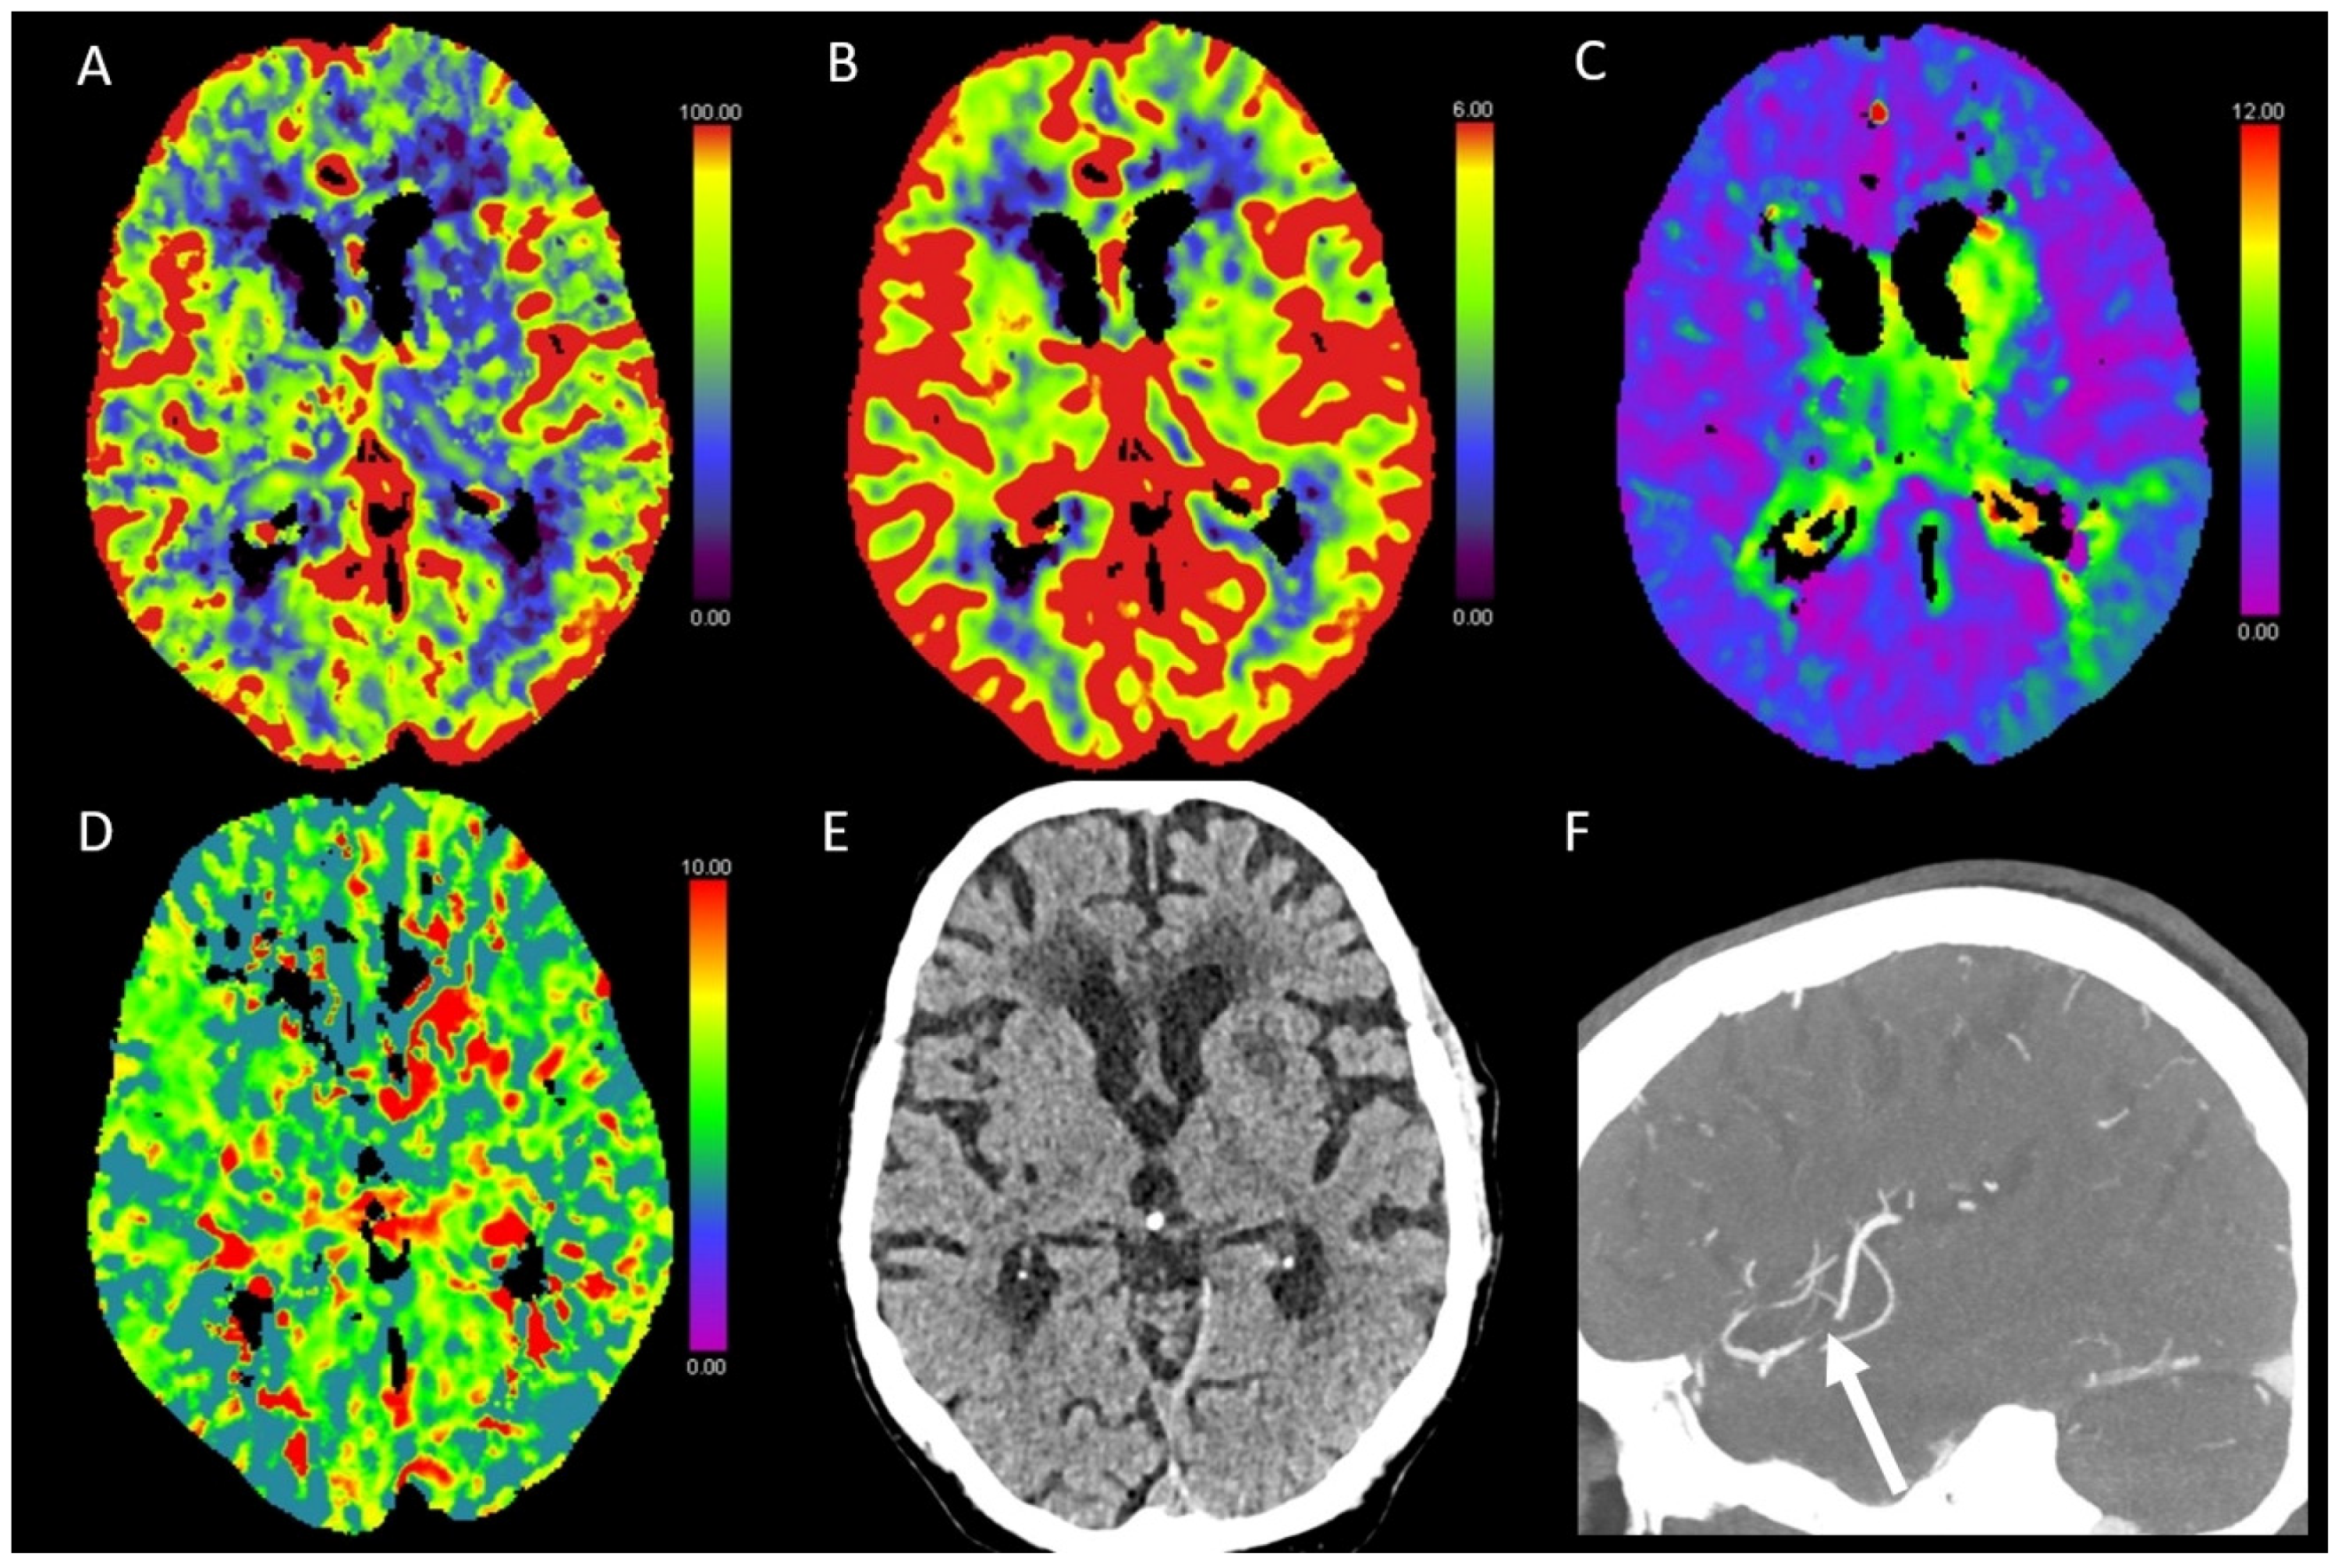

3.5. Hypotensive Cerebral Infarction (HCI) with Watershed Infarcts/Border Zones